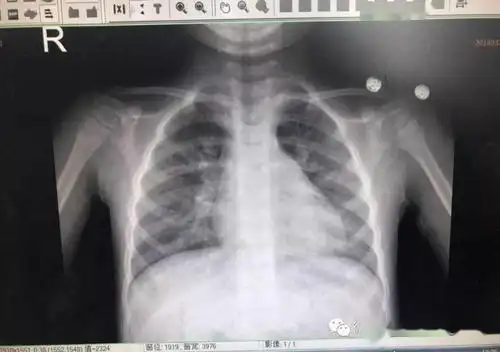

新生儿30天得肺炎,现在在妇幼icu,这是胸片,很严重吗